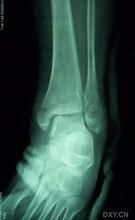

踝部骨折踝部受傷後,局部腫脹明顯,淤斑、出現內翻或外翻畸形,活動障礙,檢查可在骨折處捫局限性壓痛,踝關節正位、側位X線拍片可明確骨折的部位、類型、移位方向,對第Ⅲ型骨折,需檢查腓骨全長,若局部有壓痛。應補充照X線片,以明確高位腓骨骨折的診斷。

(1)、有明顯的外傷史。(2)上述症狀和體徵,如腫痛、畸形等。(3)X線攝片可見骨折。

踝部受傷後,局部腫脹明顯,淤斑、出現內翻或外翻畸形,活動障礙,檢查可在骨折處捫多局限性壓痛,踝關節正位、側位X線拍片可明確骨折的部位、類型、移位方向,對第Ⅲ型骨折,需檢查腓骨全長,若局部有壓痛。應補充照X線片,以明確高位腓骨骨折的診斷。